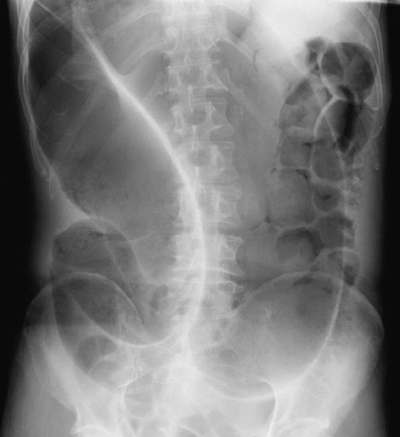

70歳の男性。激しい腹痛と腹部膨満感とを主訴に救急車で搬入された。以前から Parkinson 病で内服治療中であった。体温 36.8 ℃。心拍数 72/分、整。血圧 130/70 mmHg。呼吸数 16/分。血液所見:赤血球 420 万、Hb 11.2 g/dL、白血球 11,000、血小板 20 万。血液生化学所 見:AST 33 U/L、ALT 25 U/L。CRP 5.8 mg/dL。腹部エックス線写真を示す。

まず行うべきなのはどれか。